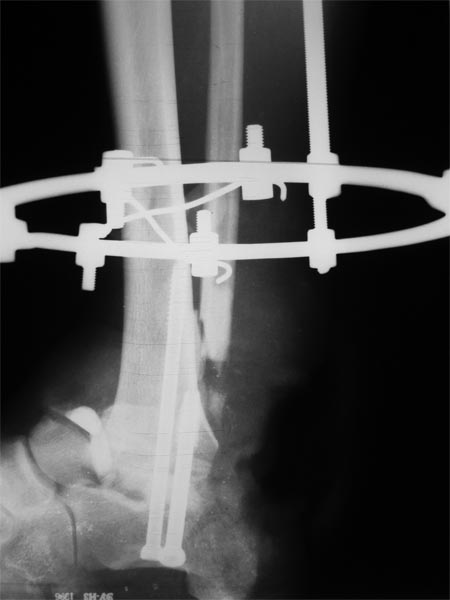

Пациенту для закрытия дефекта выполнена резекция таранной кости, пяточно-большебецовый артродез винтами. После укорочения сформировался запас тканей, достаточный для закрытия дефекта. Далее несколько дней повязка с низким давлением и свободная аутодермопластика. Пациент выписан. После окончательного заживления планируем демонтировать аппарат и перейти на циркулярную повязку. Когда по Вашему мнению следует давать нагрузку?

А на что наступать? На рентгенограмме опорная поверхность стопы не видна. Если там несросшаяся пяточная кость или ее дефект? Срок совсем маленький, ранняя нагрузка приведет к коллапсу. Может быть парциальная нагрузка? Но все равно желательно увидеть целиком дистальный конец.